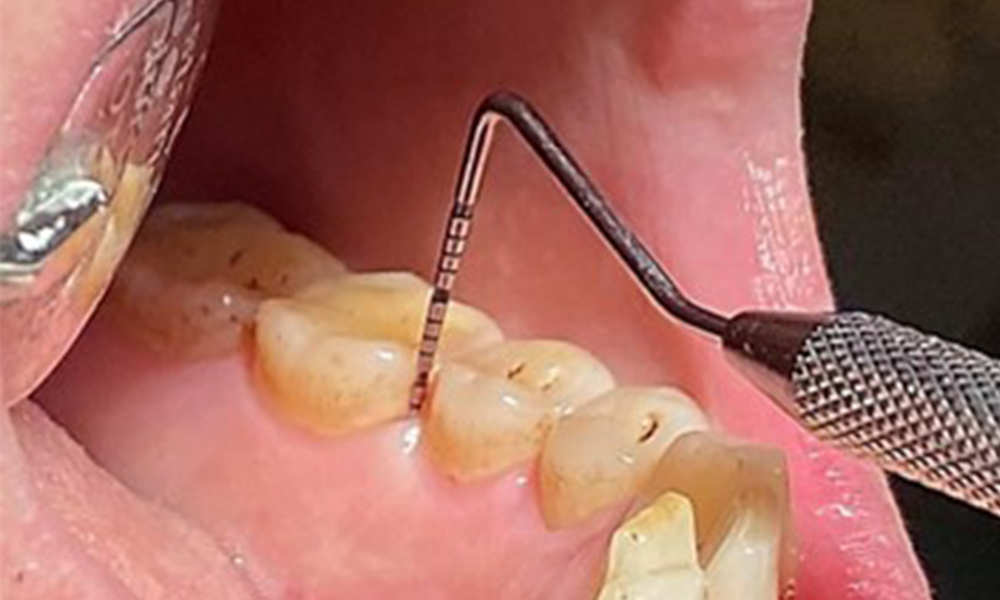

Поради иначе благоприятното общо медицинско състояние, нуждите, определени по време на оралния преглед, ще бъдат решаващи за лечението. От съществено значение ще бъде периодичното определяне на дълбочината на сондиране. Гингивалното кървене намалява при пушачите, поради което клиничната диагноза на пародонтита може да се постави само чрез сондиране (фиг. 7). Поставянето на изключителен акцент върху определянето на индексите на кървене може да замъгли съществуващ пародонтит или гингивит. (5)

- Важно е да се документират резултатите от контролния преглед. По време на всяка среща трябва да се определя статусът на кървене при сондиране (BOP) за измерване на дълбочината на пародонталния джоб в ранните етапи на заболяването. Това е особено важно при пушачите поради намален приток на кръв към тъканите.